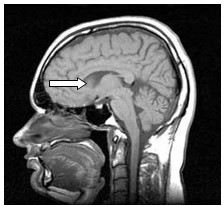

Na rentgenogramie przedstawione jest złamanie Saltera-Harrisa typu

Ilustracja do pytania 19

A. II odcinka bliższego kości piszczelowej.

B. V czwartej kości śródręcza.

C. I ześlizgnięcie bliższej nasady kości udowej lewej.

D. III nasady dalszej kości piszczelowej.